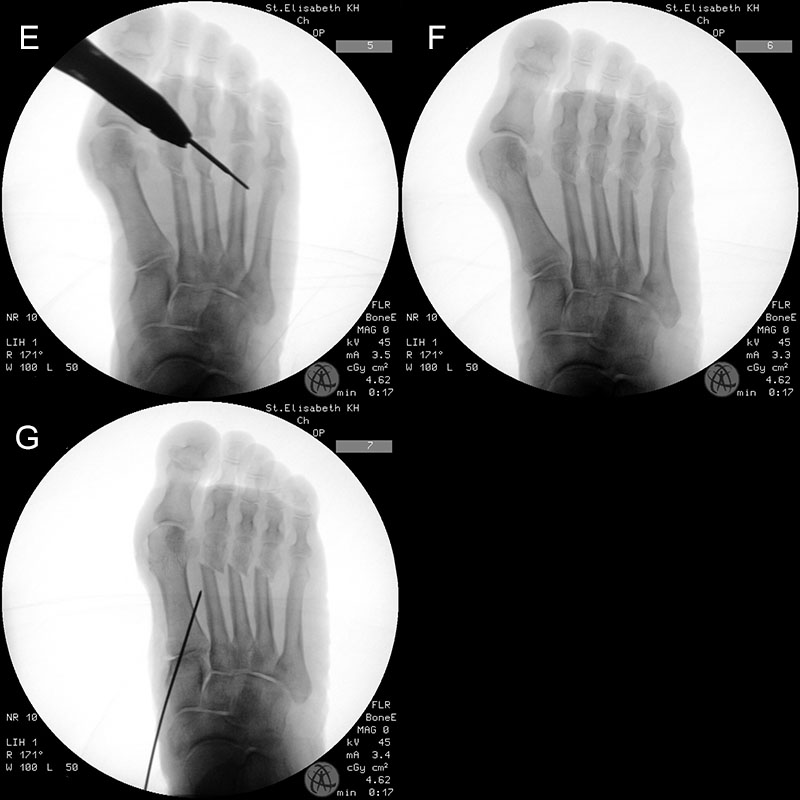

Zum Lesen der Bildbeschreibung und zur Vollansicht bitte die Bilder anklicken.